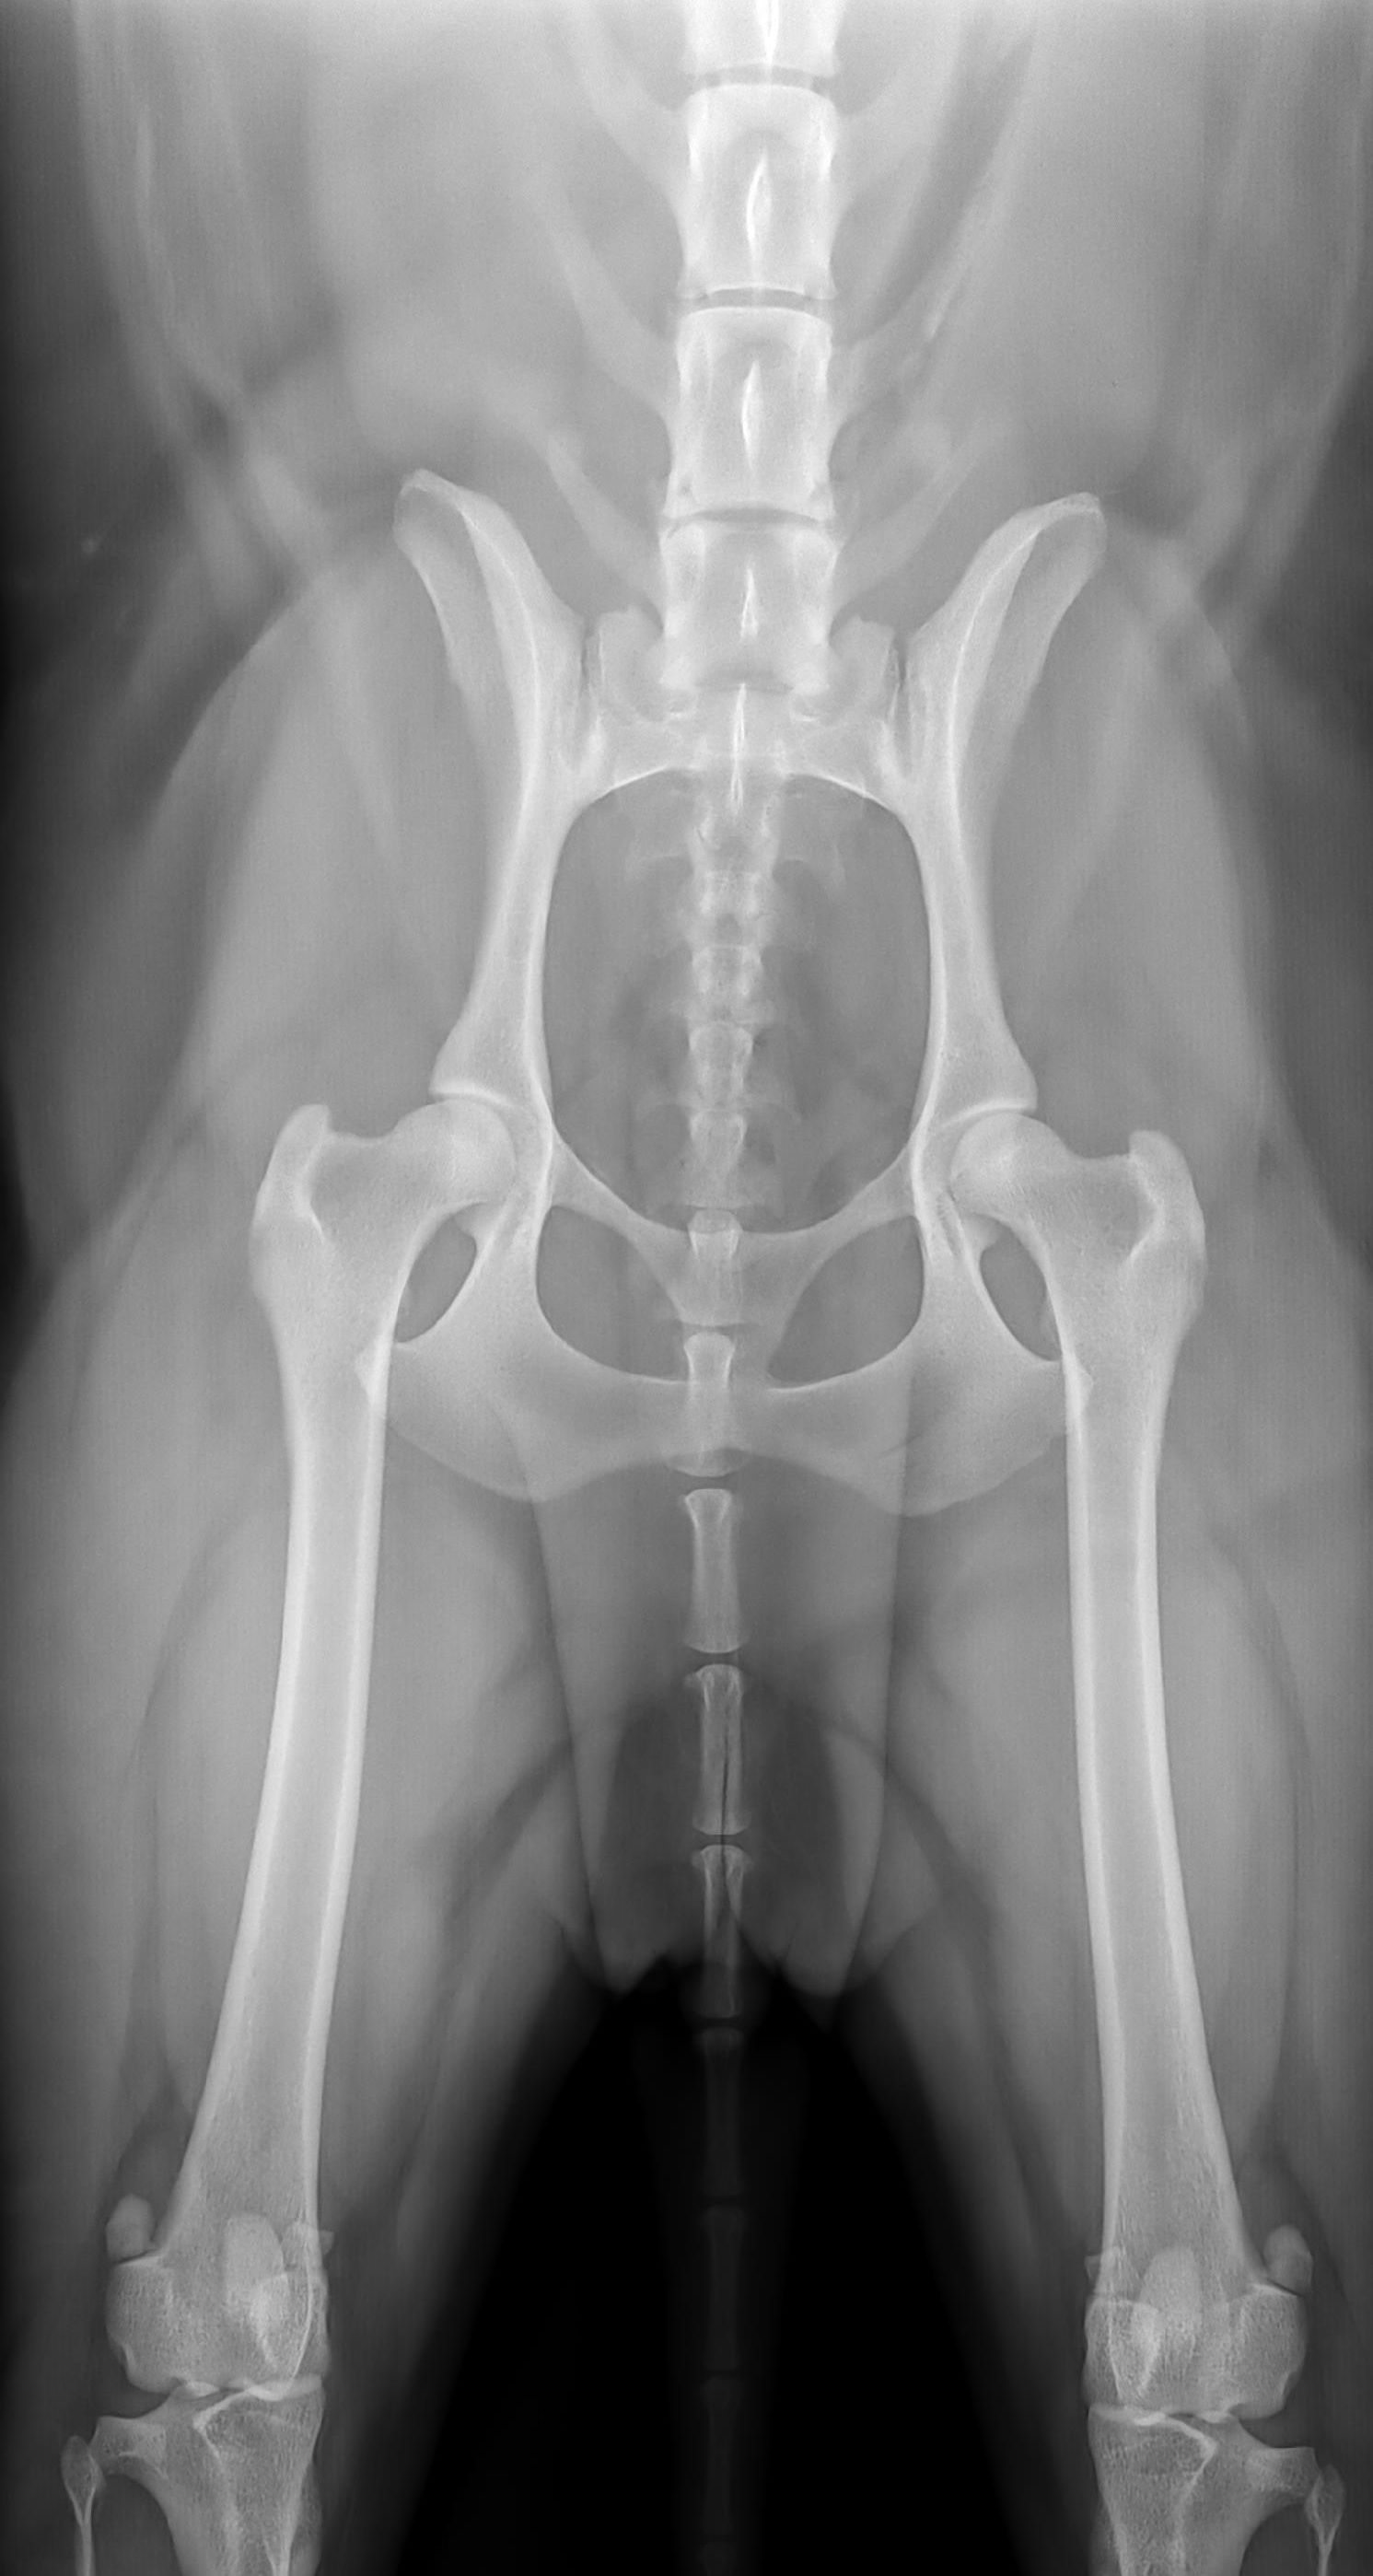

Röntgen Becken einer dreijährigen gesunden Golden-Doodle-Hündin

Becken